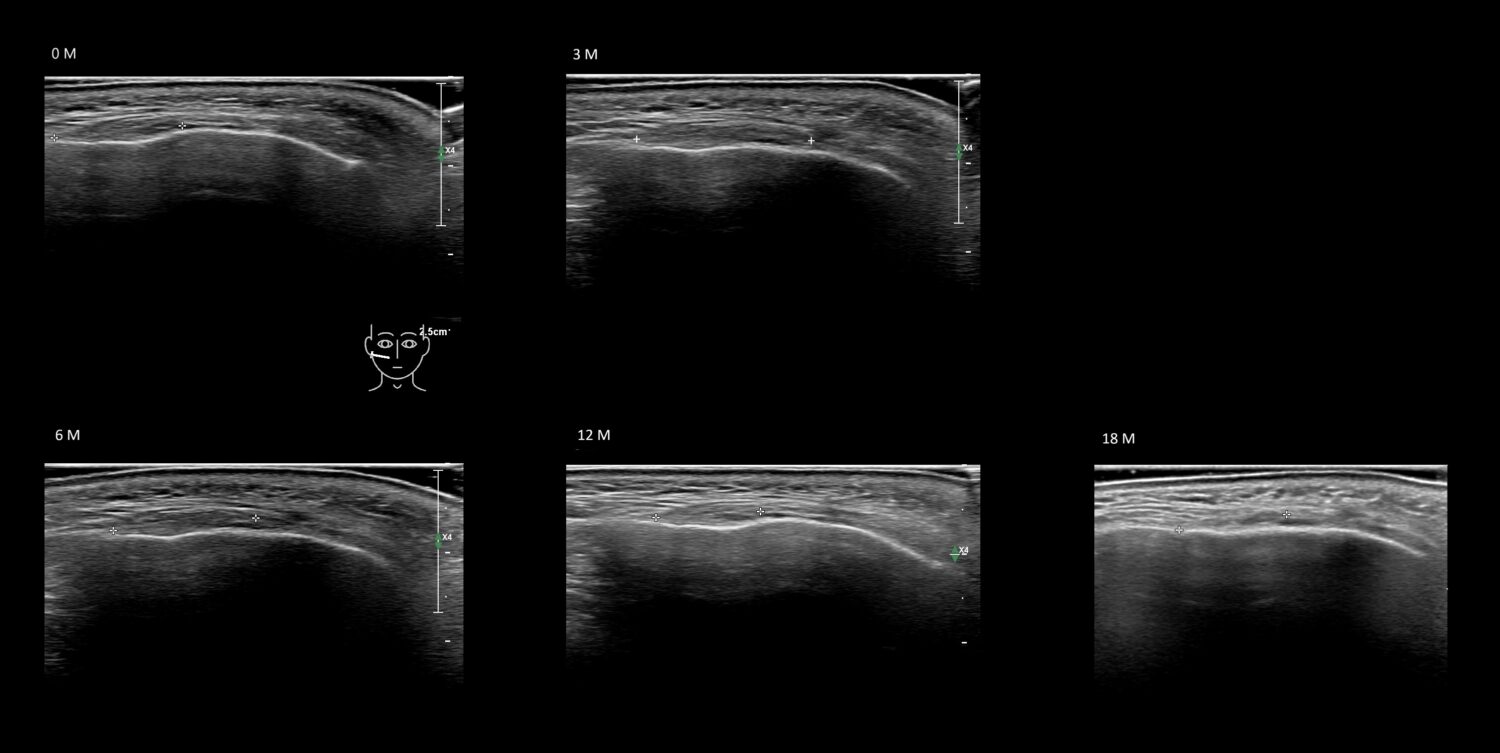

Filler library